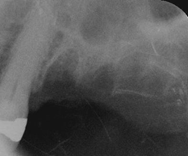

Depois de curetado os alvélos, foram preenchidos com material aloplástico: Gengimix + Adesivo cirúrgico. Para manutenção do material enxertado a ferida cirúrgica foi recoberta com uma membrana de colágeno reabisorvível. Neste procedimento é importante o material ser bem comprimido e protegido, não haverá sangramento após a intervenção. p22p21Importante notar que as raízes do primeiro molar foram seccionadas, para a nutenção do alvéolo remanescente, o segundo molar não houve necessidade deste procedimento. Depois de colocada a membrana tudo foi muito bem suturado, e colocado cimento cirúrgico. p23p24Estas são as duas radiografias a primeira, logo após a cirurgia e curetagem dos alvélos, (ela está invertida, para comparação). A segundo é após o preenchimento dos alvélos com material de ROG.